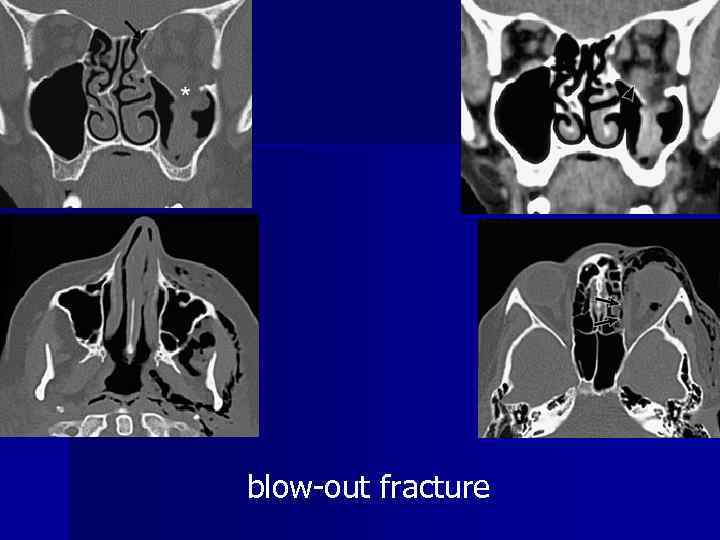

Facial trauma blow-out fracture